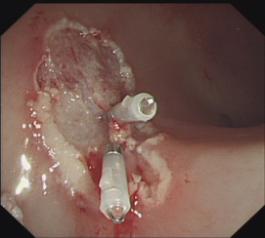

3. 食管曲张静脉硬化剂注射、套扎术及胃底静脉曲张组织胶注射栓塞术:在全市首先开展,处领先水平;

食管曲张静脉出血套扎术

胃底曲张静脉改良“三明治”注射